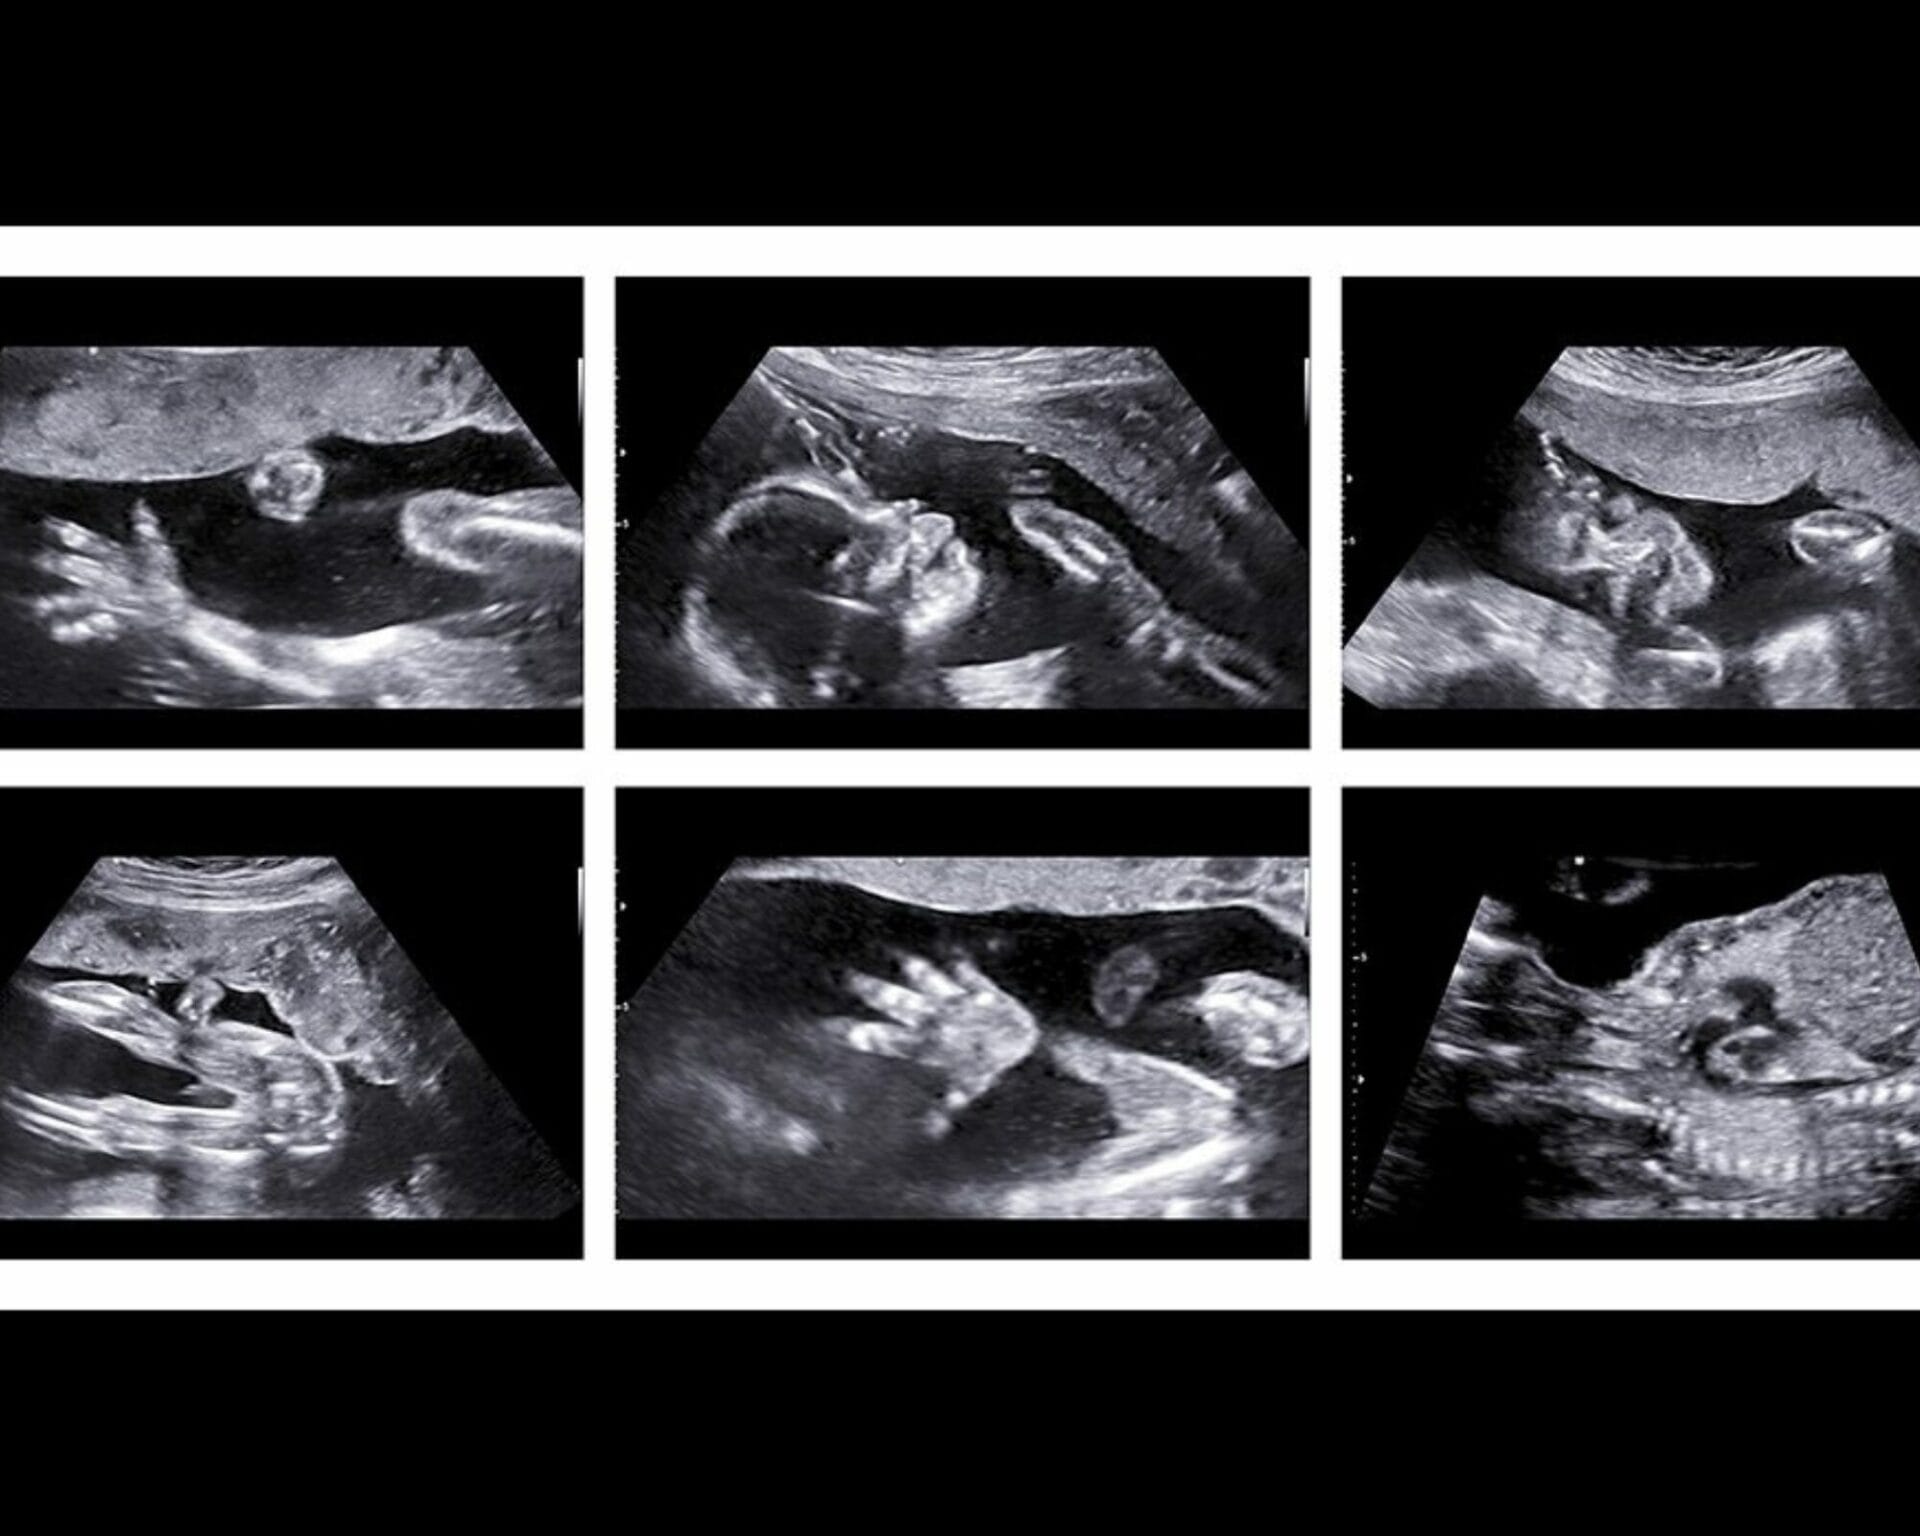

عند ذهابك الى الطبيبة سيتم قياس طفلك للتأكد من أن نموه يسير على الطريق الصحيح، وسيتم فحص الأجهزة الرئيسية المناسبة مثل قياسات الجنين في الرأس والبطن وعظم الفخذ، رأس الجنين والصدر والبطن، وجه الجنين، والعمود الفقري الجنيني وفحص الأطراف، وسيتم فحص السائل الأمنيوسي وموقع المشيمة ومعدل ضربات قلب الجنين للتأكد من صحة الطفل، وسوف يُظهر الفحص أيضًا موضع المشيمة في الرحم والمناطق المحيطة بها مثل الأورام الليفية، أو أكياس المبيض وعنق الرحم المغلق

قد يتم في بعض الأحيان التعرف على المشيمة النازلة (حيث يتم ربطها بالجزء السفلي من الرحم) عند الفحص لا تقلقي كثيرًا كما هو الحال في 90 % من الحالات بينما ينمو طفلك، يسحب رحمك الموسع بشكل طبيعي المشيمة لأعلى بعيدًا عن عنق الرحم بالنسبة لبعض النساء لا تزال المشيمة تقع في الجزء السفلي من الرحم بعد 20 أسبوعًا.

إذا كانت المشيمة تمنع فتح الرحم جزئيًا أو كليًا في نهاية فترة الحمل فإن هذا يُعرف باسم” المشيمة البريفيا ” .

هذا يؤثر على 1 من كل 200 ولادة ومع ذلك إذا ثبت أن المشيمة تغطي عنق الرحم عند إجراء الفحص فسيتم تقديم مسح آخر بين 32 إلى 36 أسبوعًا للتحقق من انتقاله.